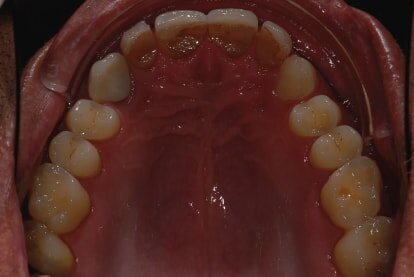

In 2015, a 47-year-old male patient presented complaining of pain in the TMJ. He also had an aesthetic request, since part of the veneer on one of the maxillary central incisors had broken off (Figs. 1–3). The clinical and radiographic analysis (Fig. 4) indicated a loss of bite height and tooth substance due to bruxism.

Fig. 1: Intraoral photograph prior to treatment, frontal view.